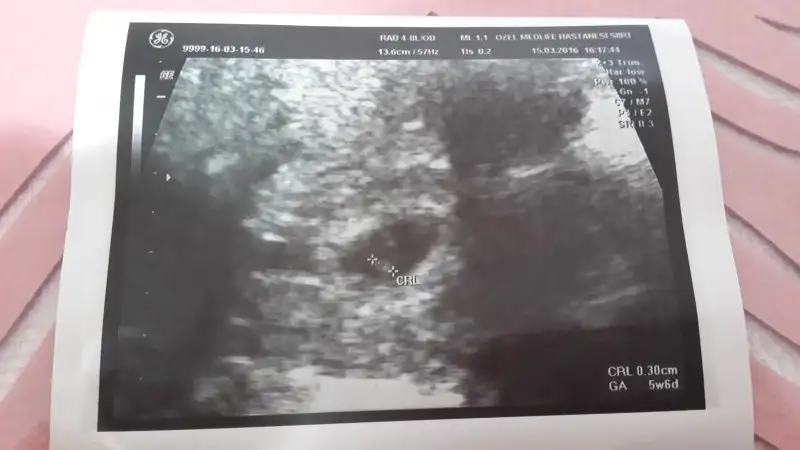

Karnımdan usg canım 7+2günlük..sağolasın merakla bekliyorımUsg karındansa erkek gibi,vajinalsa kız gibi cnm

saga daha yakin kiz gibi rabbim bilir gonlunuzdeki olur insallahKızlar bana da bir tahminde bulunabilir misiniz 5+5 günlük Burda ve vajinal bakıldı

vajinalsa sol canim erkek o zaman galibaKızlar bana da bir tahminde bulunabilir misiniz 5+5 günlük Burda ve vajinal bakıldı